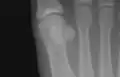

The first metatarsal. (Left.)

The first metatarsal bone is the bone in the foot just behind the big toe. The first metatarsal bone is the shortest of the metatarsal bones and by far the thickest and strongest of them.[1]

Like the four other metatarsals, it can be divided into three parts: base, body and head. The base is the part closest to the ankle and the head is closest to the big toe. The narrowed part in the middle is referred to as the body of the bone. The bone is somewhat flattened, giving it two sides: the plantar (towards the sole of the foot) and the dorsal side (the area facing upwards while standing).[1]